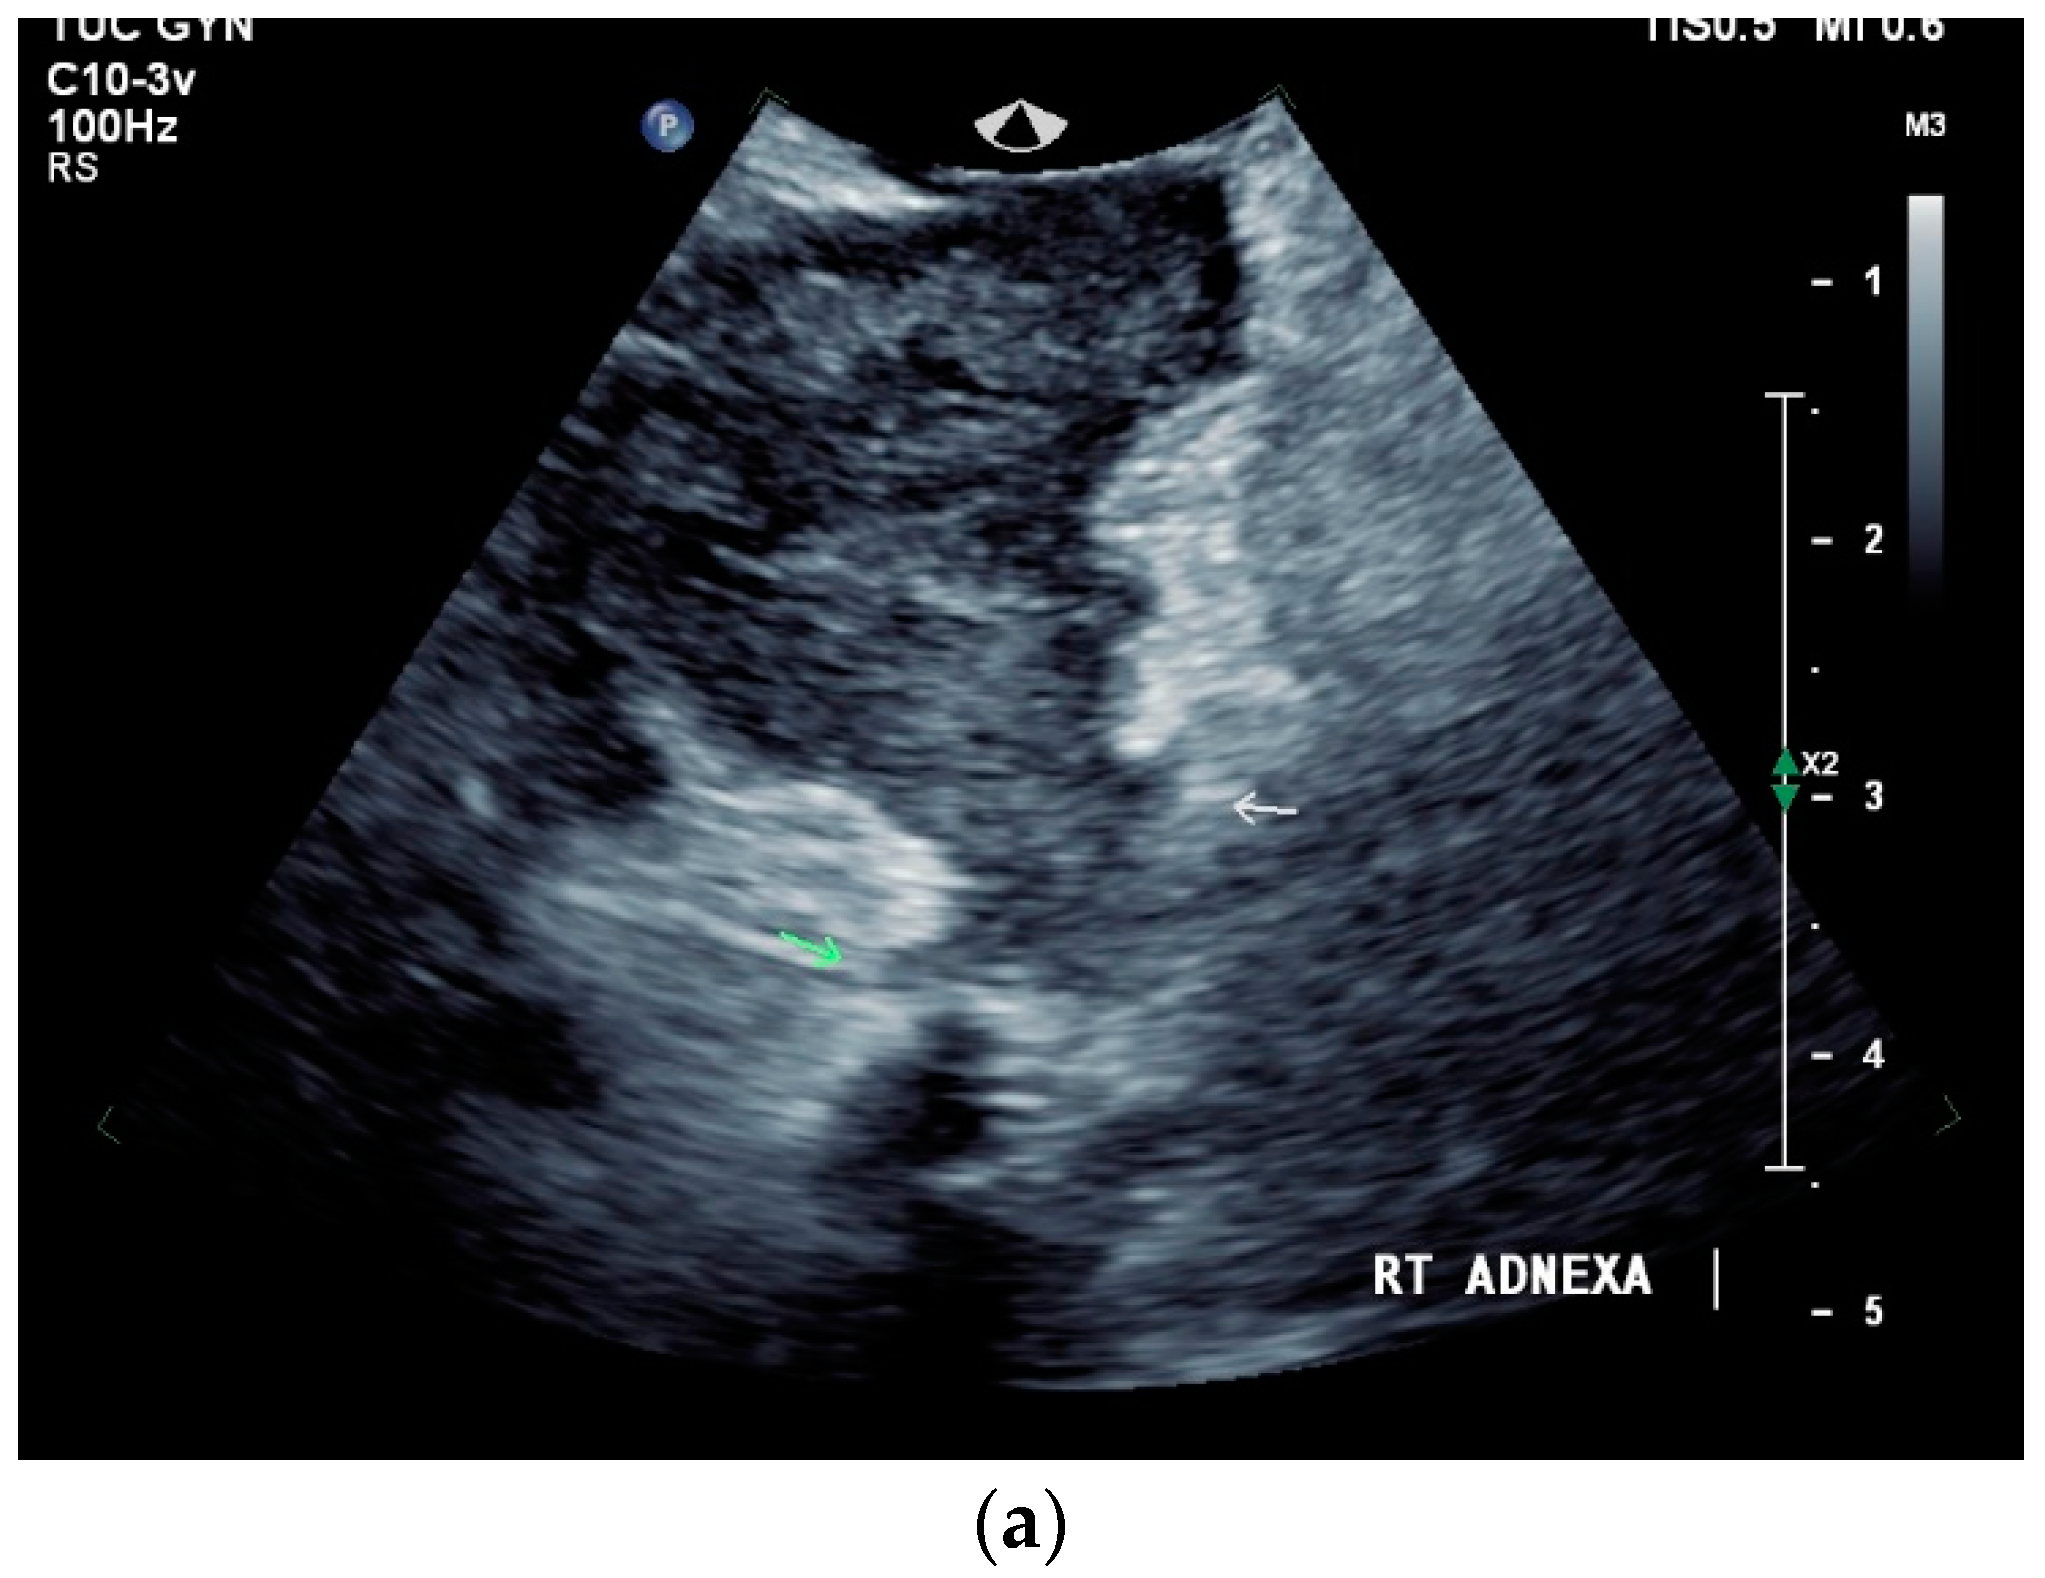

Signs of tuberculosis in abdominal or vaginal ultrasounds in the female genital area are ovarian cyst, tubo-ovarian mass, hydrosalpinx, pyosalpinx, adhesion, adnexal fixation, thin endometrium, endometrial fluid, endometrial calcification, endometrial synechiae (Asherman’s syndrome), cornual synechiae, disturbed endometrial vascularity, ascites in the small pelvis, and peritoneal or omental thickening [122]. In a study with 175 infertile patients, ovarian cysts (23.4%) and tubo-ovarian masses (15.4%) were the most common manifestations [122] [Figure 8a–e].

Figure 8.

Tuberculosis of the uterus and adnexae. Female patients with tuberculosis in India. Pelvis with tubo-ovarian masses: Hypoechoic lesion in right adnexa (arrows) (a) and hypoechoic lesion in left adnexa and a small amount of free fluid (arrows) (b). Free fluid in the Douglas space (arrows) (c). Thickened right fallopian tube (RT FT) (arrows) (d); thickened left fallopian tube (LT FT) (arrows) (e).